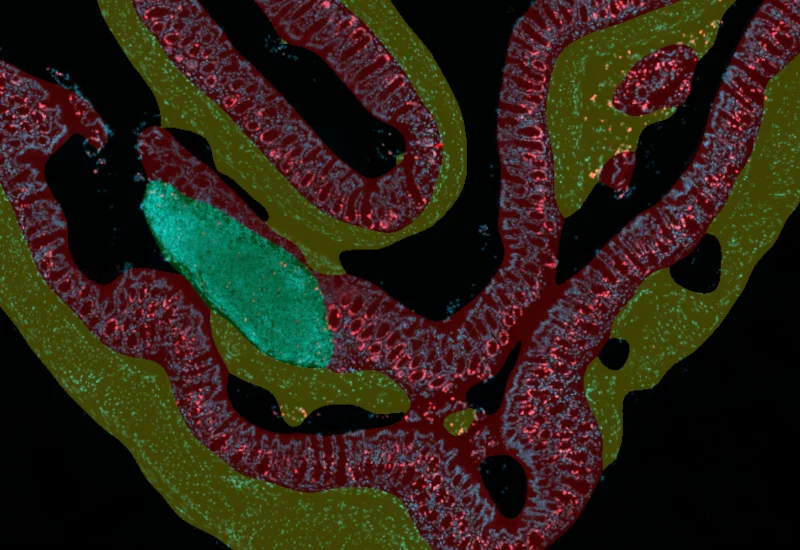

The IF Swiss Roll App segments tissue into subclasses (e.g., mucosa, follicles, connective tissue), detects nuclei, and identifies phenotypes via IF stains.

The IF Swiss Roll App allows for detection of the swiss roll, and the segmentation into different subclasses (mucosa, immune cell follicles, connective tissue, background). Further it detects nuclei and identifies phenotypes based on specific IF stains. The App outputs area (µm2) of detected tissues/tissue classes, count of total cells as well as in each detected area. Count and % of specific phenotype detected in total as well as in the tissue classes.

Nuclei and Phenotype detection